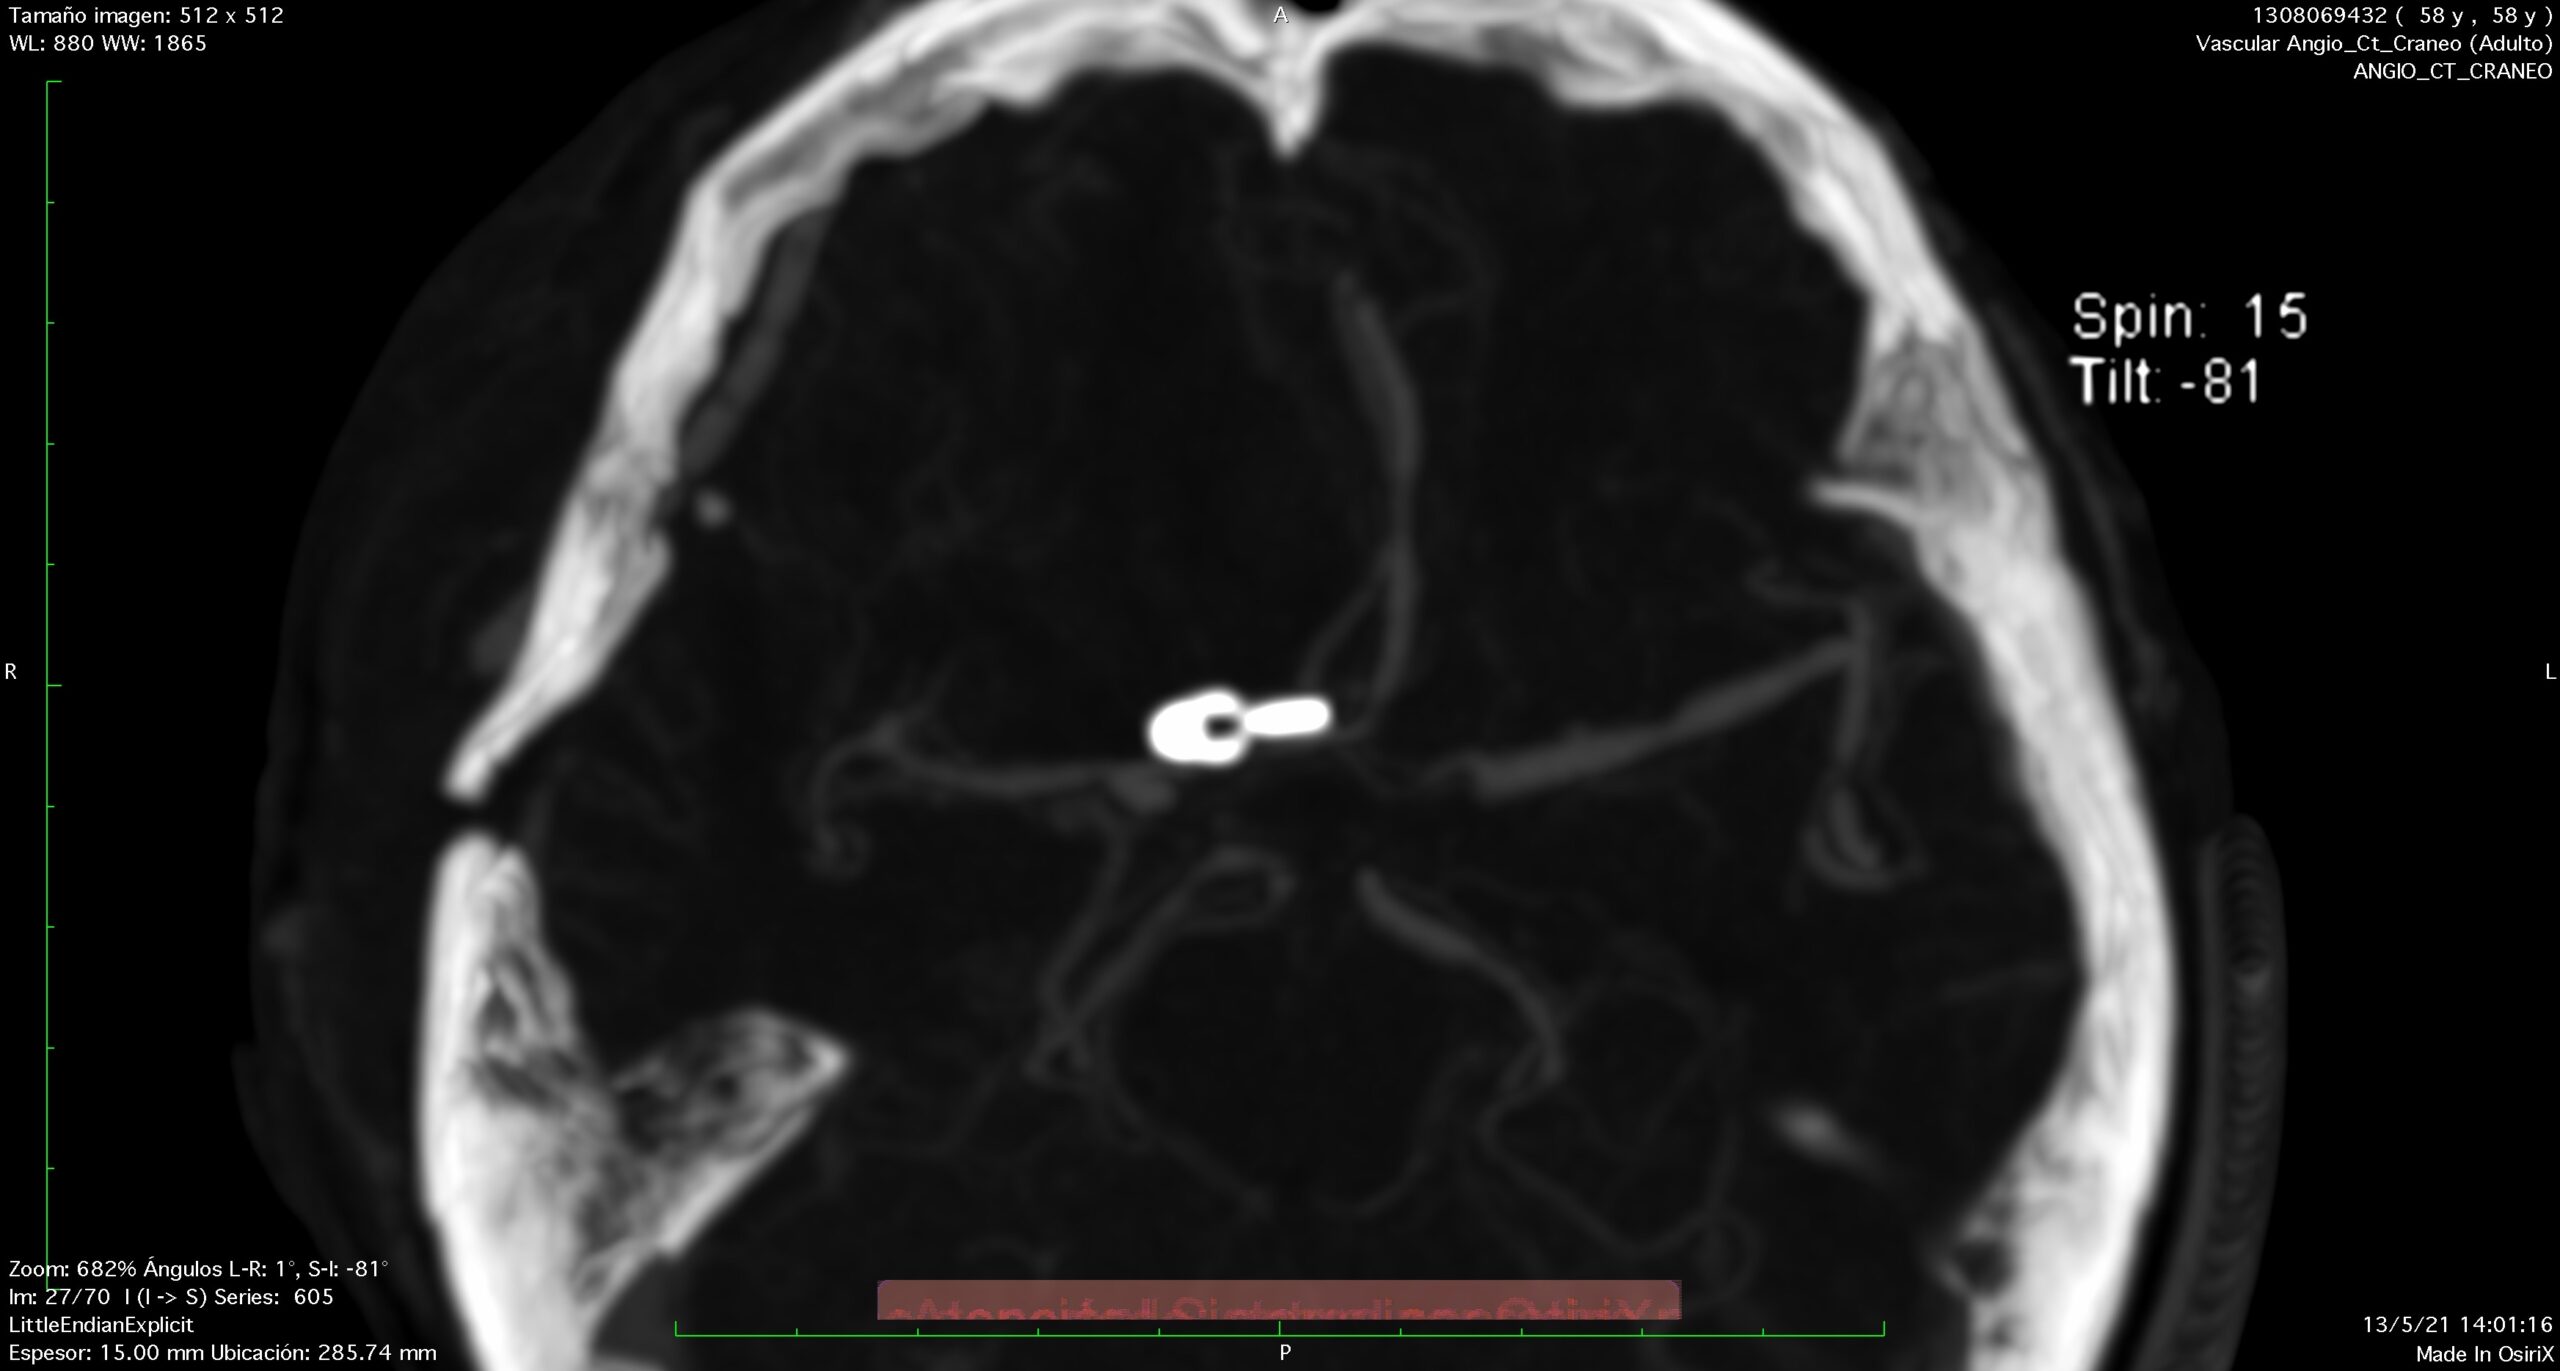

El patrón de hemorragia típico que se observa después de la ruptura de un aneurisma. La forma y la ubicación del aneurisma pueden predecir su comportamiento y también determinar qué opción de tratamiento es probable que sea la mejor. Alternativamente, si el aneurisma representa un bajo riesgo de ruptura o un alto riesgo quirúrgico, podemos optar por seguirlo con imágenes en serie. La intervención está diseñada para detener el flujo de sangre hacia el aneurisma, eliminando así el riesgo de hemorragia. Se puede realizar de forma endovascular rellenando el aneurisma desde dentro («coiling» endovascular), o mediante técnicas microquirúrgicas abiertas («clipaje»).

Aneurisma recurrente visto cerca de clips

Angiografía cerebral 3D que muestra un aneurisma